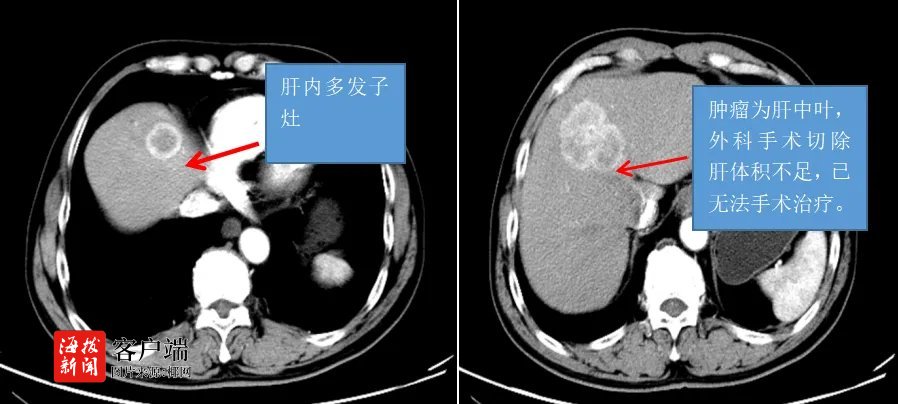

2023年7月,王老伯因腹痛、乏力、食欲下降在家属的陪同下来到海南医科大学第一附属医院(以下简称海医一附院)肝胆胰外科就诊,肝胆胰外科医生给予王老伯查增强CT检查。检查结果提示:肝左内叶占位,考虑原发性肝癌(巨块型)并肝内子灶形成。王老伯有长期的乙肝病史,并且未接受抗病毒规范治疗,所以这可能是王老伯罹患肝癌的原因。

该院肝胆胰外科专家团队认为王老伯肝脏肿瘤较大,分期较晚,外科手术切除难度较大,剩余肝脏不足,已无法开展常规手术治疗。宋奇峰副主任医师与患者及其家属沟通后,决定为王老伯制定肝动脉灌注化疗HAIC+免疫+靶向的治疗方案。